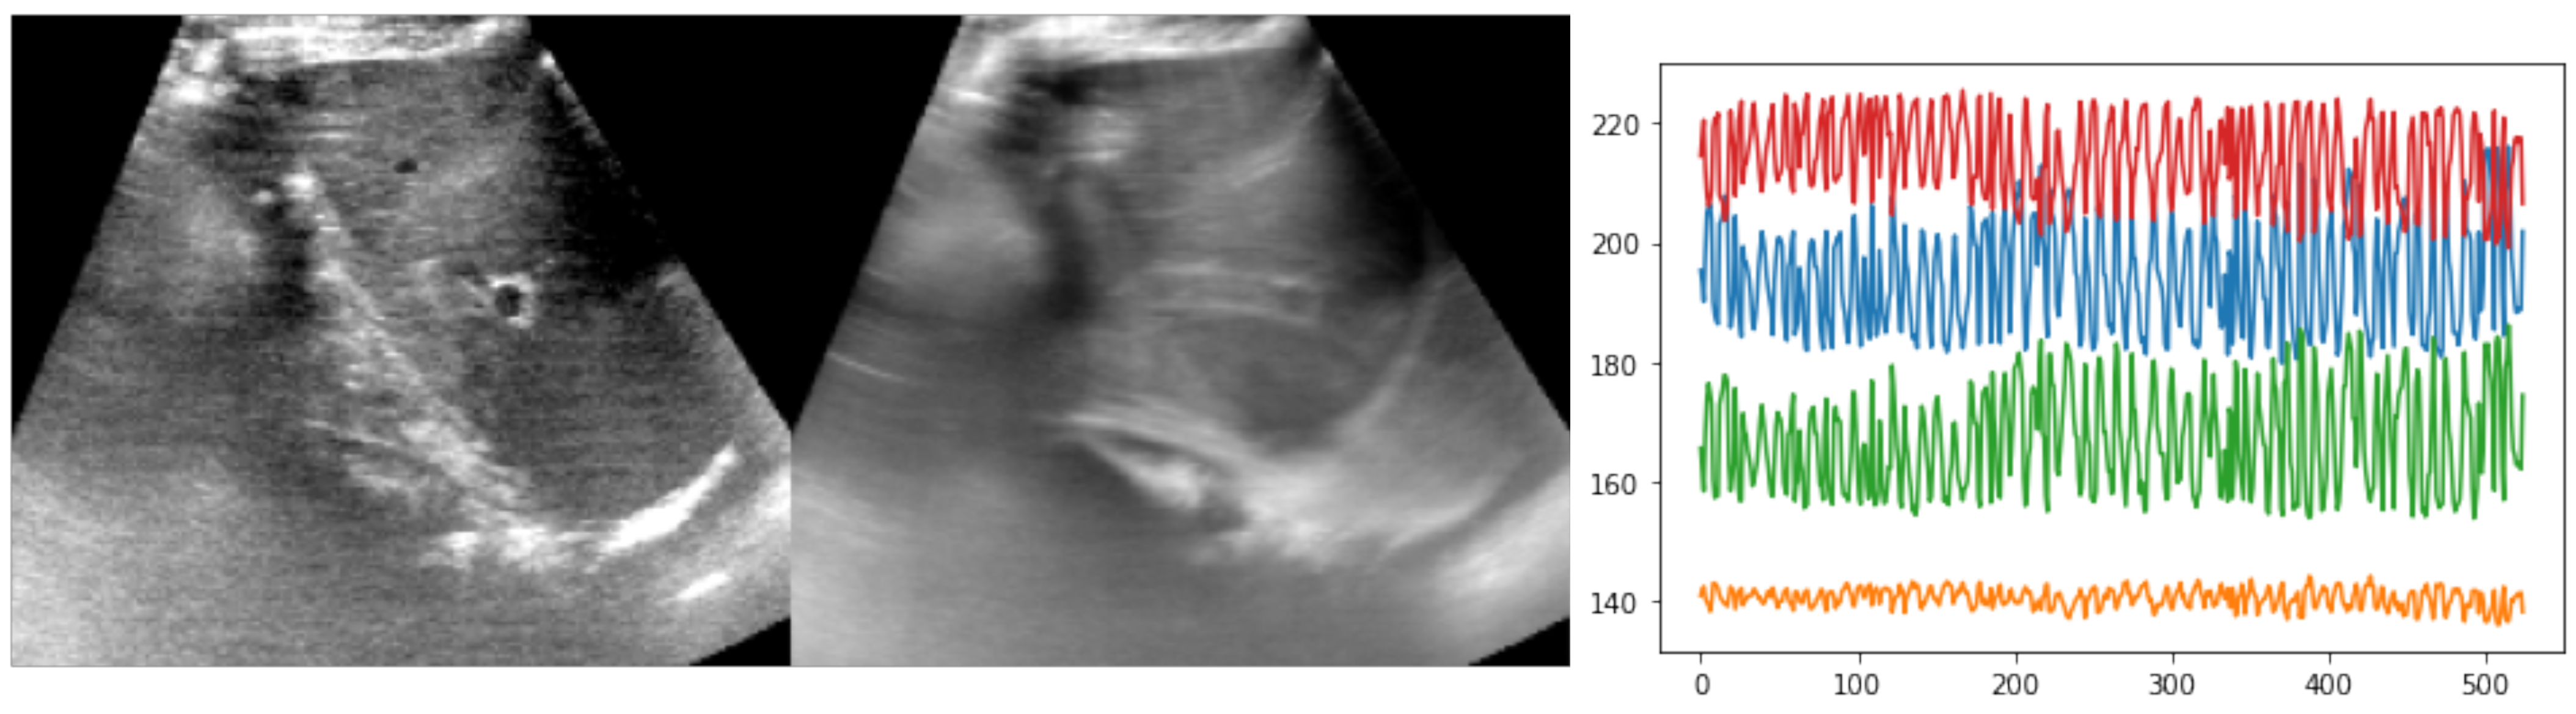

The public CLUST dataset https://clust.ethz.ch/data.html (acccessed on 6 May 2022) comprises several 2D ultrasound sequences of healthy volunteers freely breathing with multiple different scanners and transducers [1]. Here, we focused on ten sequences of several hundred frames each from the ETHZ dataset (see Figure 4). The temporal resolution was 15 Hz but higher frequencies were easily achievable with newer ultrasound probes. The image dimensions were approximately 400 × 400 pixels, with a square resolution of 0.4 mm. Either one or two anatomical landmarks were manually annotated by experts along each sequence to serve as both training objective and for cross-validation of the test accuracy. About a tenth of frames were labeled by three annotators to compute the inter-rater variance. The expected motion could reach several centimetres in each direction, i.e., motion of 16 pixels or more had to be estimated. So far, nearly all state-of-the-art approaches have used either temporal consistency (often coupled with online learning or fine-tuning) or restricted the search to a predefined template region. In our experiments, the whole image was used without cropping, and bilinearly downsampled to 160 × 192 pixels.

Figure 4. Example of reference frame and temporal average across one sequence from the ETHZ dataset, along with a plot of the observed motion, based on expert annotations (xy-coordinates for two landmarks). The temporal average, which showed substantial blurring of anatomies over time, as well as the large and rapid xy-coordinate changes in the annotations highlighted the difficulty of the registration task.